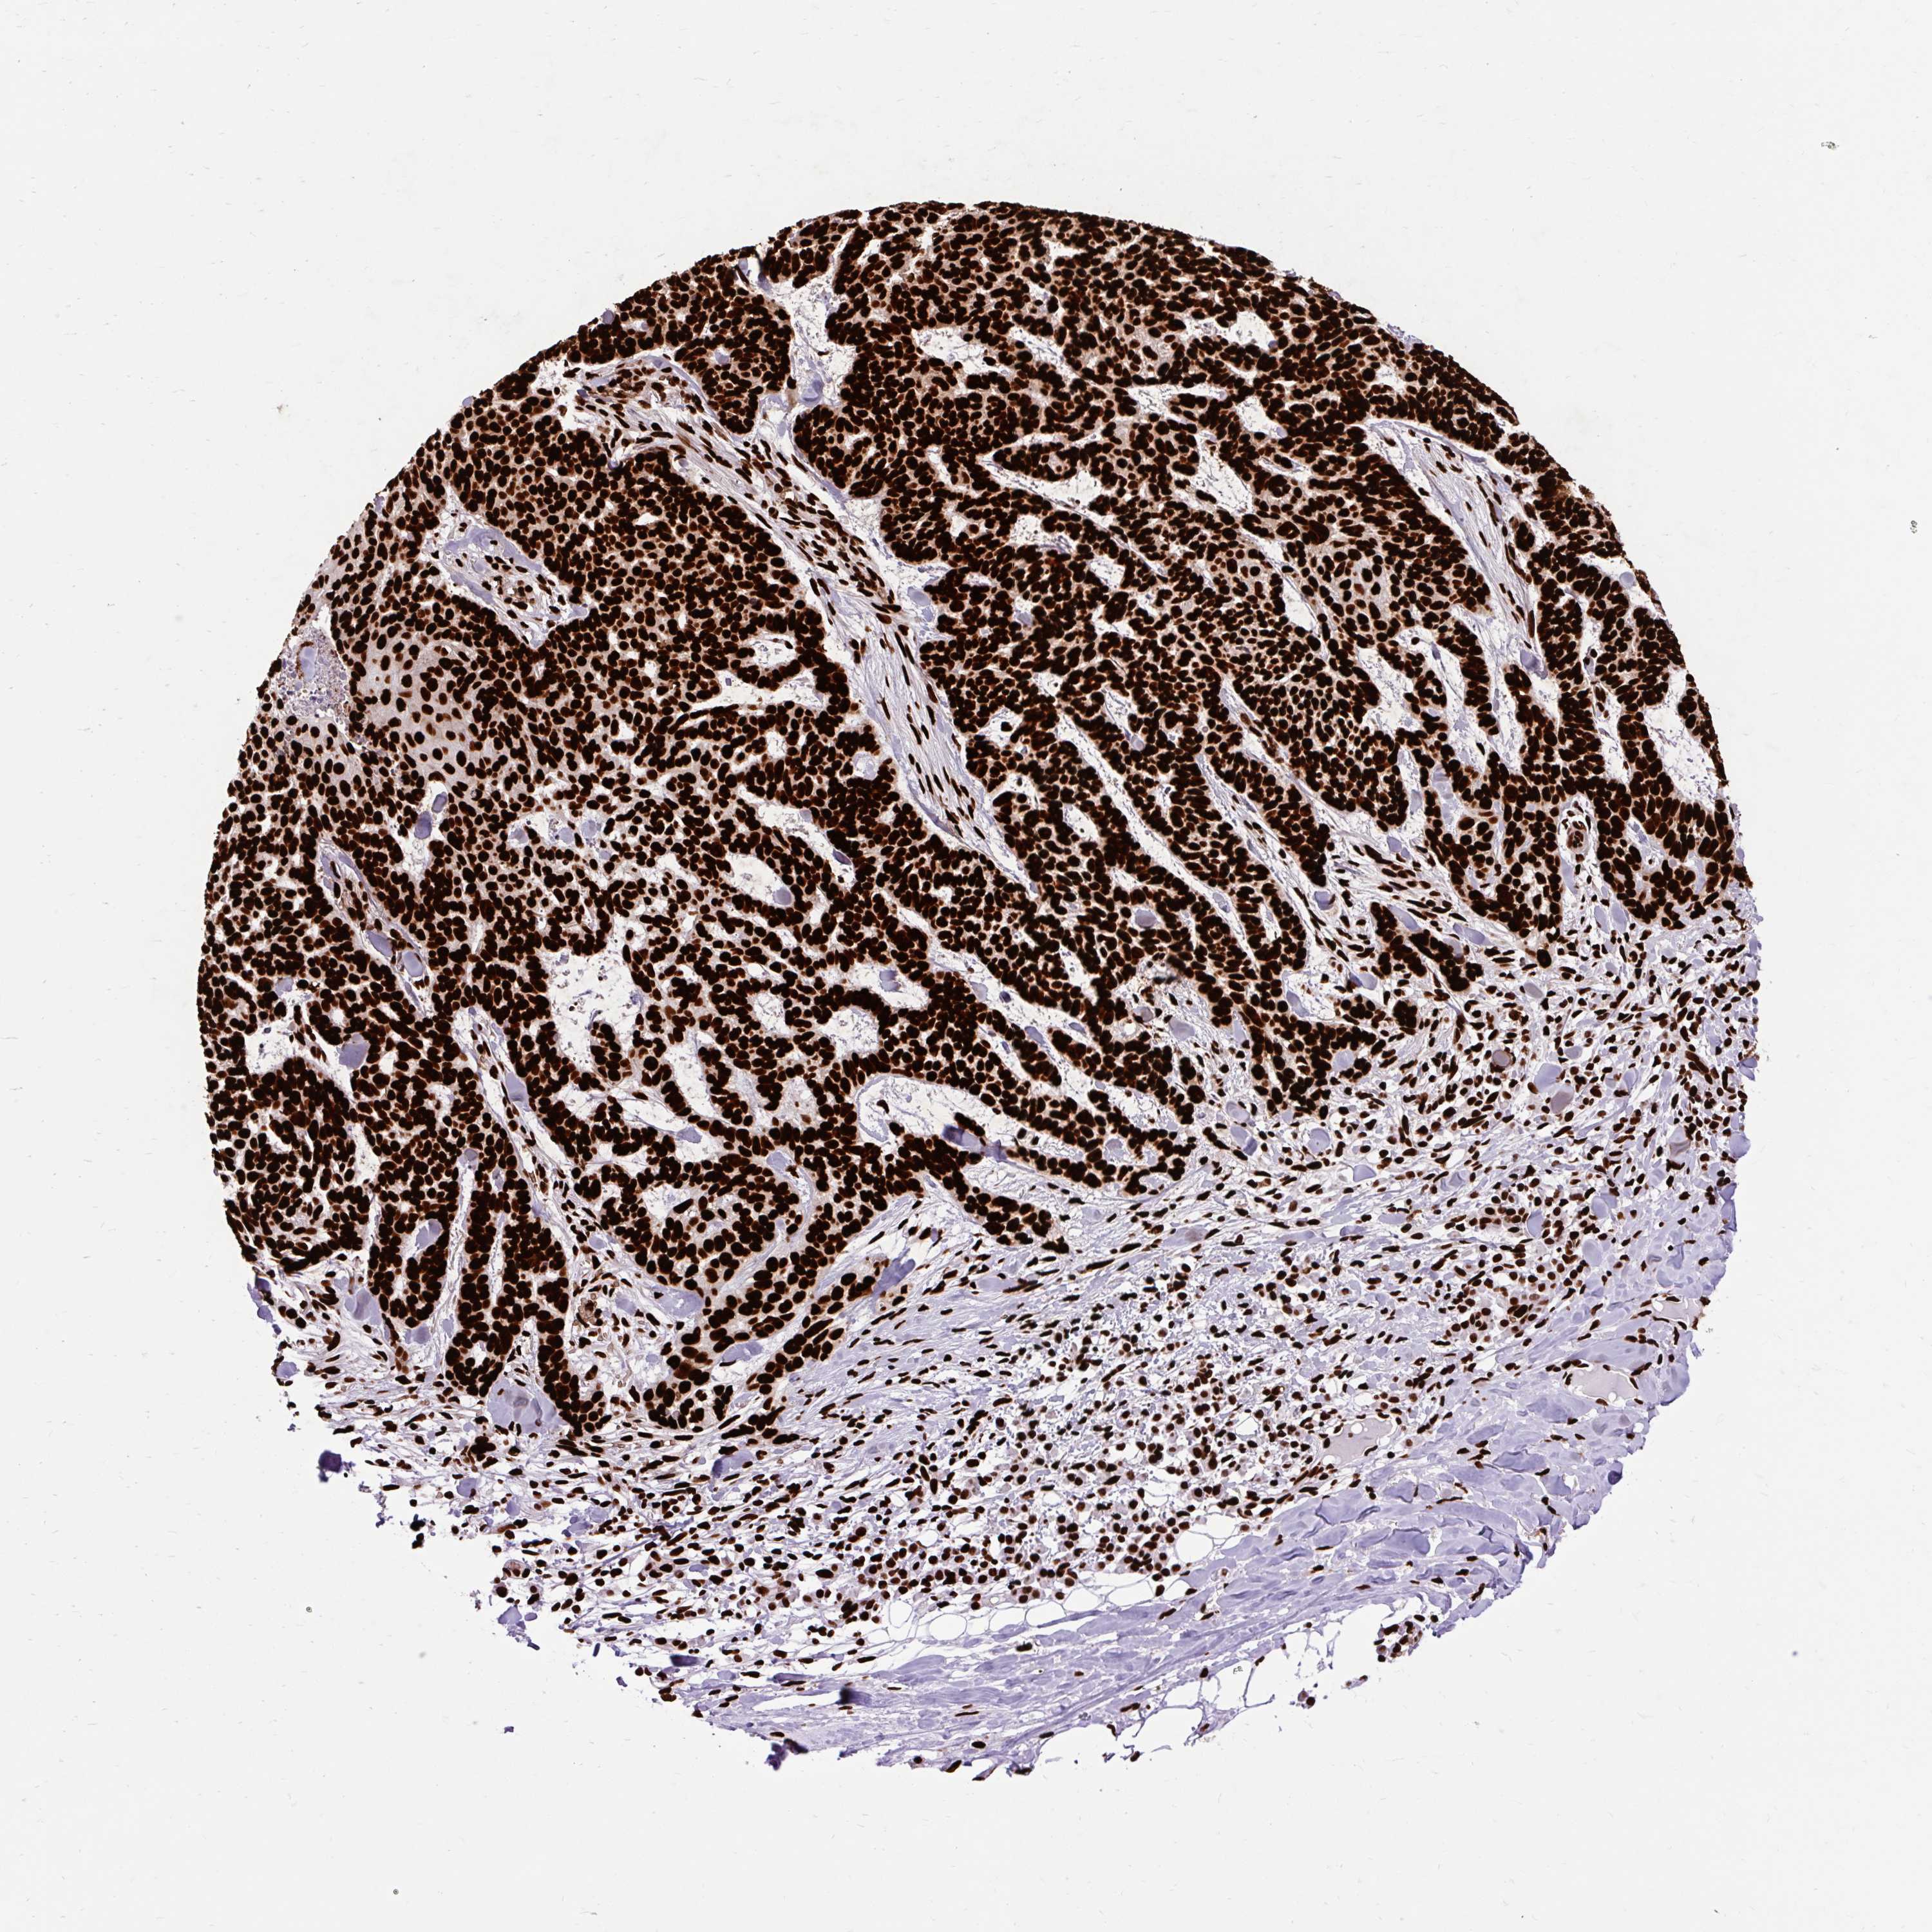

SKIN CANCER - Protein expressioni

A mouse-over function shows sample information and annotation data. Click on an image to view it in a full screen mode. Samples can be filtered based on level of antibody staining by selecting one or several of the following categories: high, medium, low and not detected. The assay and annotation is described here.

Antibody stainingi

Antibody staining in the annotated cell types in the current human tissue is reported as not detected, low, medium, or high, based on conventional immunohistochemistry profiling in selected tissues. This score is based on the combination of the staining intensity and fraction of stained cells.

Each image is clickable and will lead to virtual microscopy that enables deeper exploration of all samples and also displays staining intensity scores, fraction scores and subcellular localization as well as patient and tissue information for each sample.

Antibody HPA008784

Antibody CAB033036

Antibody CAB058691

Squamous cell carcinoma, NOS

Squamous cell carcinoma, metastatic, NOS

Basal cell carcinoma

Papilloma, NOS